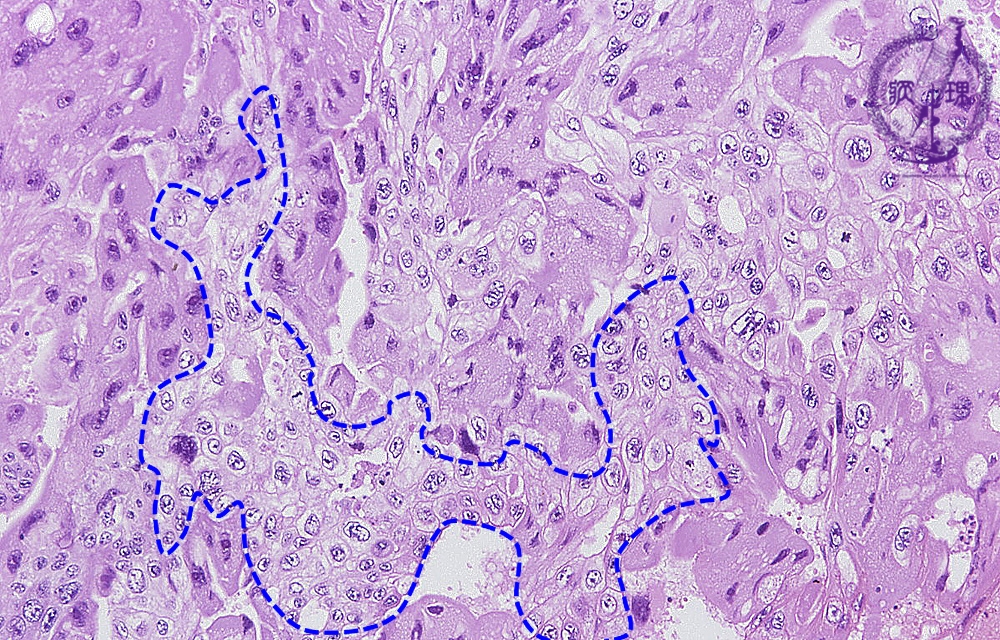

Histology (HE stain, low power):Multinucleated eosinophilic tumor cells mimicking syncytiotrophoblasts, (yellow dotted line) and tumor cells with clear cytoplasm mimicking cytotrophoblasts (blue dotted line) proliferate in sheet-like pattern. The former type of tumor cells produces and secretes human chorionic gonadotropin (h-CG) as identified by IHC (see below).